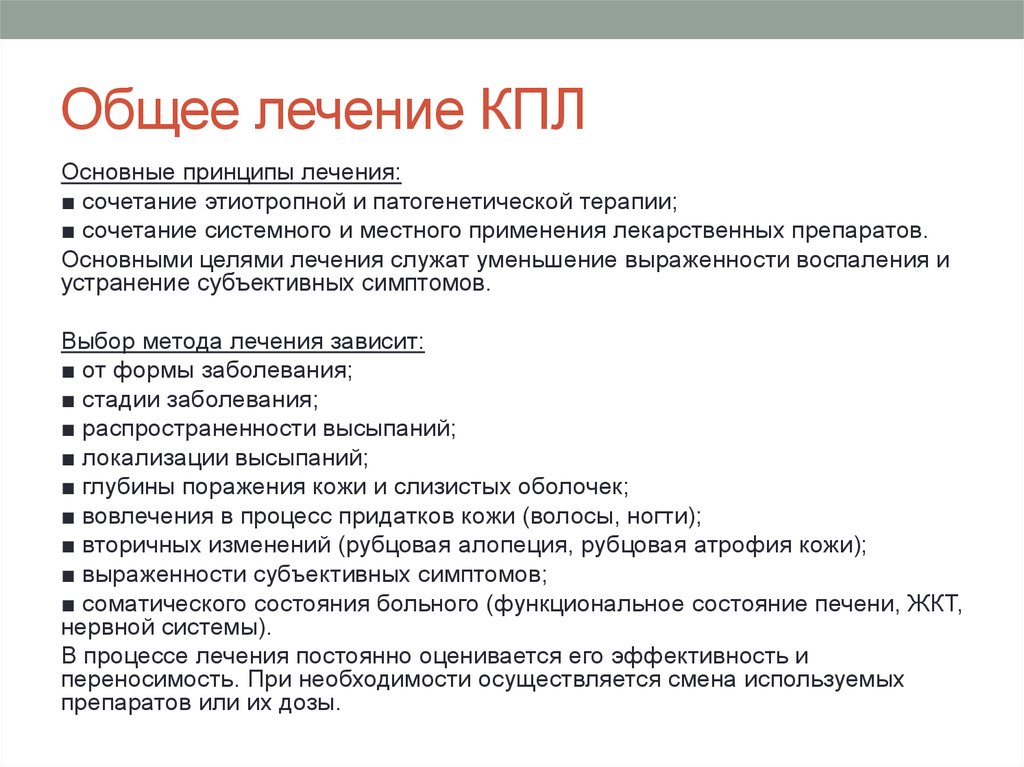

Фото Красного Плоского

Фото Красного Плоского 103 фото